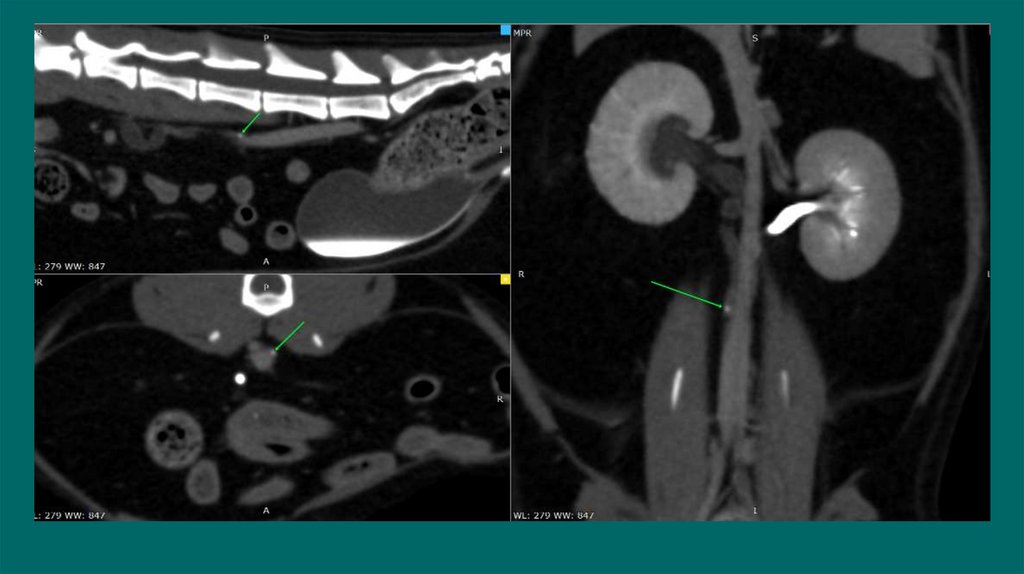

42. Пиелография

Определения локализации обструкции мочеточников у кошек с азотемией

Снижен риск попадания контраста в почки при нефропатии

Техника

Проводится под УЗИ контролем.

Тонкоигольная аспирация содержимого из лоханки(пиелоцентез)

Спинальной иглой или иглой диаметром 22G вводят под углом 45

Введение йодсодержащего контраста йода(Омнипак,Урографин)

Объем контрастного вещества должен составлять половину объема аспирационной мочи

Dominique Penninck, Marc-Andre d Anjou.2008-2015

40. Экскреторная урография

Рентгенологическое исследование с внутривенным введением контраста .

Показания:

Субъективно функцию почек СКФ, пиелоэктазию, гидронефроз, оценить проходимость

мочеточников, обнаружение эктопии мочеточников ,обнаружении разрывов на уровне от

мочеточников до мочевого пузыря